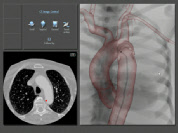

PROcedure Rehearsal Studio loads your patient’s CT and MRI data onto Simbionix ANGIO Mentor, the world’s leading virtual reality endovascular simulator. Within a few minutes of a scan, you can practice complete endovascular procedures on your patient from the safety of a simulator.

PROcedure Rehearsal Studio lets you use fluoroscopy, guidewires, catheters and other cath lab equipment to experience true-to-life tactile feedback of a real procedure on a virtual model of your own patient with

your patient’s anatomy, physiology and diagnostic anomalies.